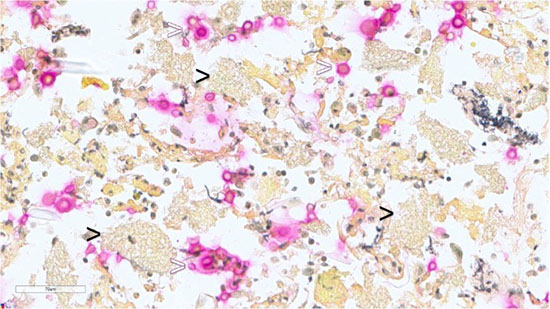

Figure 4: Lung FNA, Cell Block, GMS stain: highlights Pneumocystis jirovecii (black arrowheads) and Cryptococcus species (white arrowheads).

Figure 5: Lung FNA, Cell Block, Mucicarmine stain: highlights mucinous capsule of Cryptococcus species (white arrowheads) and negative in foamy amorphous materials (black arrowheads).

P. jirovecii does not grow in vitro; hence, a definitive diagnosis requires the demonstration of cysts or trophozoites in lung tissue or respiratory specimens such as bronchoalveolar lavage. The cyst forms of P. jirovecii appear as thick-walled, approximately 5-8 µm round structures with up to eight intracystic bodies. Trophozoite forms are smaller pleomorphic structures with a size of 1-5 µm and contain a single nucleus. The organisms are not visible with Papanicolaou stains but appear as green, foamy alveolar casts. Grocott-methenamine silver stain is used to visualize the cyst form of P.jiroveci. Giemsa stain of air-dried smear is useful to identify the cystic form as negative images, and the intracystic bodies and trophozoite as blue dots. More advanced techniques such as immunofluorescence microscopy and molecular methods are available for higher sensitivity and specificity for the detection of the pathogen.

Cryptococcus organisms are narrow-based budding yeasts with variable sizes ranging from 4- 15 μm, with a thick mucin capsule, appearing as clear spaces around yeast cells in H&E stain. Diagnosis is crucial due to potential dissemination to the central nervous system, which has a high mortality rate. Mucicarmine and GMS stains are essential for diagnosing cryptococcosis. Fungal culture and MALDI-TOF MS are available for species identification.